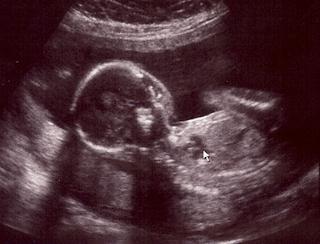

tak F. sa so mnou chysta na to d sono...tiež teraz so mnou nebol, ale vybavila som fotečky konečne...mal mi ich naskenovat, tak to idem pozriet a skusim pripojit 🙂)))))

nase bublinky s bavia medzi sebou, su otocene k sebe a netvaria sa, že nám chcu povedať že kto je kto 😀 😀 😀 ale doky povedal, že urobime coskoro to 3D, takže tam ......verim......že to vyjde .-)))))

@orsulka tak to ja beriem s rezervou - veď lax aj noe mali pekné fotečky a tiež majú dievčatká.